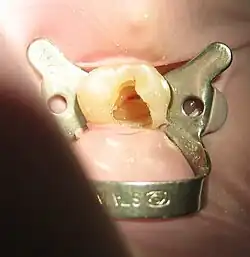

![]() Tooth #13, the upper left second premolar, after excavation of DO decay. There was a carious exposure into the pulp chamber (red oval), and the photo was taken after endodontic access was initiated and the roof of the chamber was removed. | |

Opening in the crown

The endodontist makes an opening through the enamel and dentin tissues of the tooth, usually using a dental drill fitted with a dental burr.

Isolating the tooth

The use of a rubber dam for tooth isolation is mandatory in endodontic treatment for several reasons: